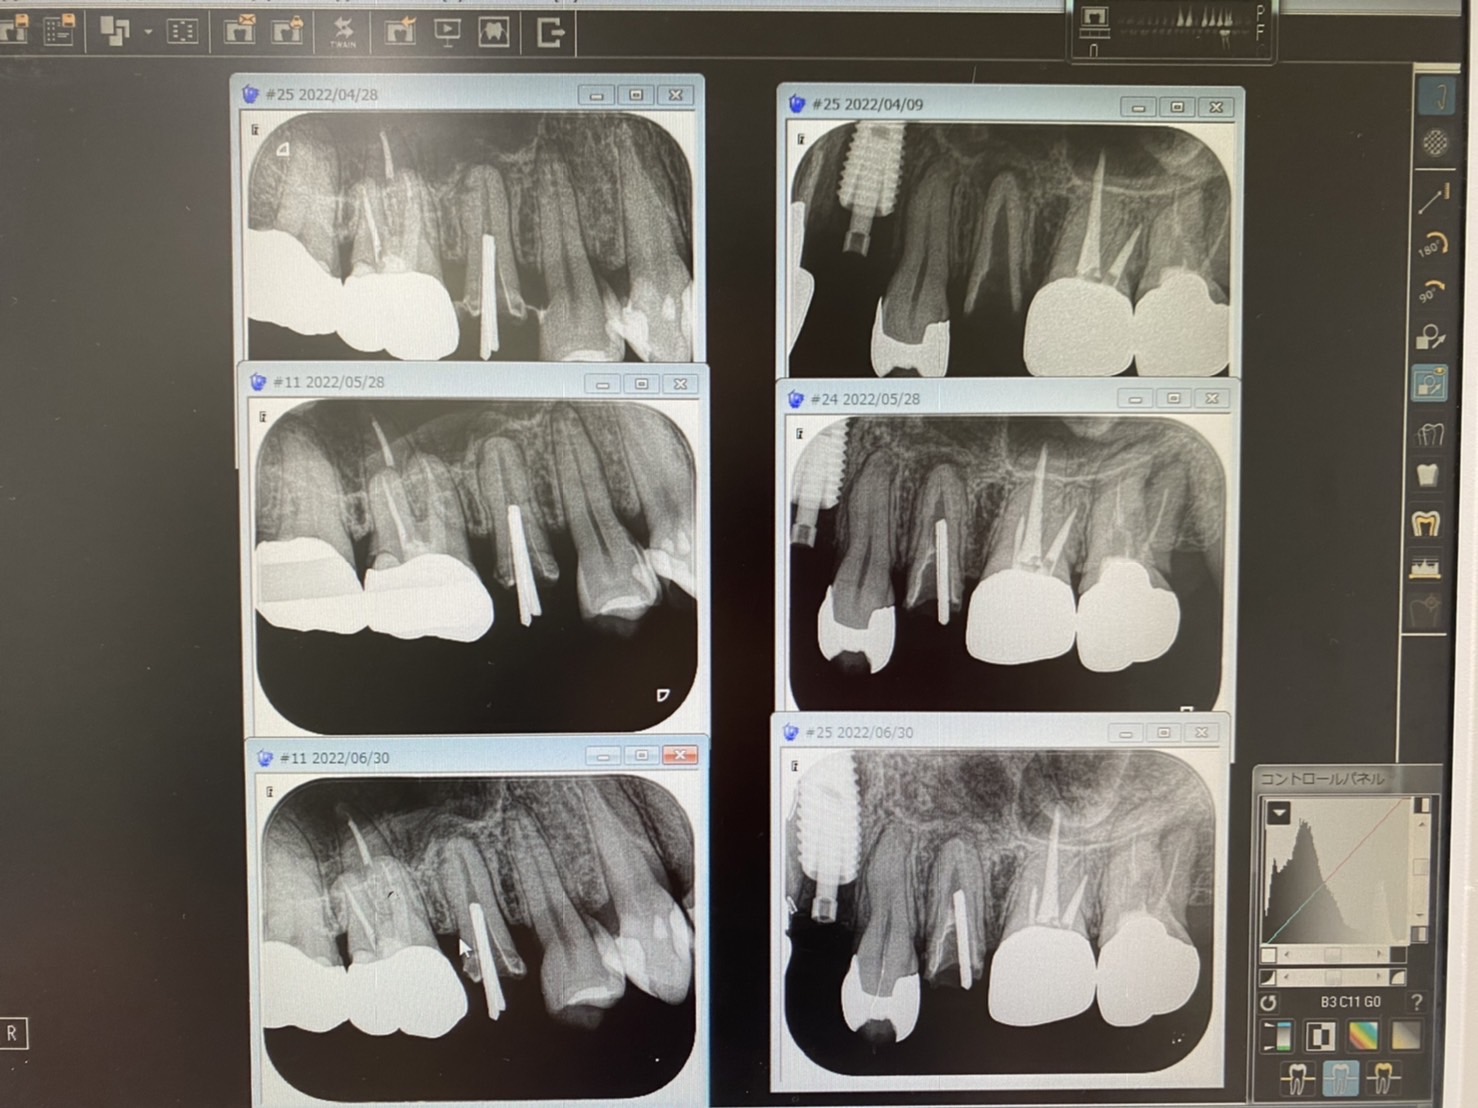

本日午後の楽しみは、2カ月間根管治療してる綺麗なコマダム様

左右5番の根尖病巣により洞低膜が破れ副鼻腔炎になったり、押し上げられたりと〜 仮歯を外しながら、無菌化を目指して 目安の2カ月、goodだぜ! 次回は根充だね